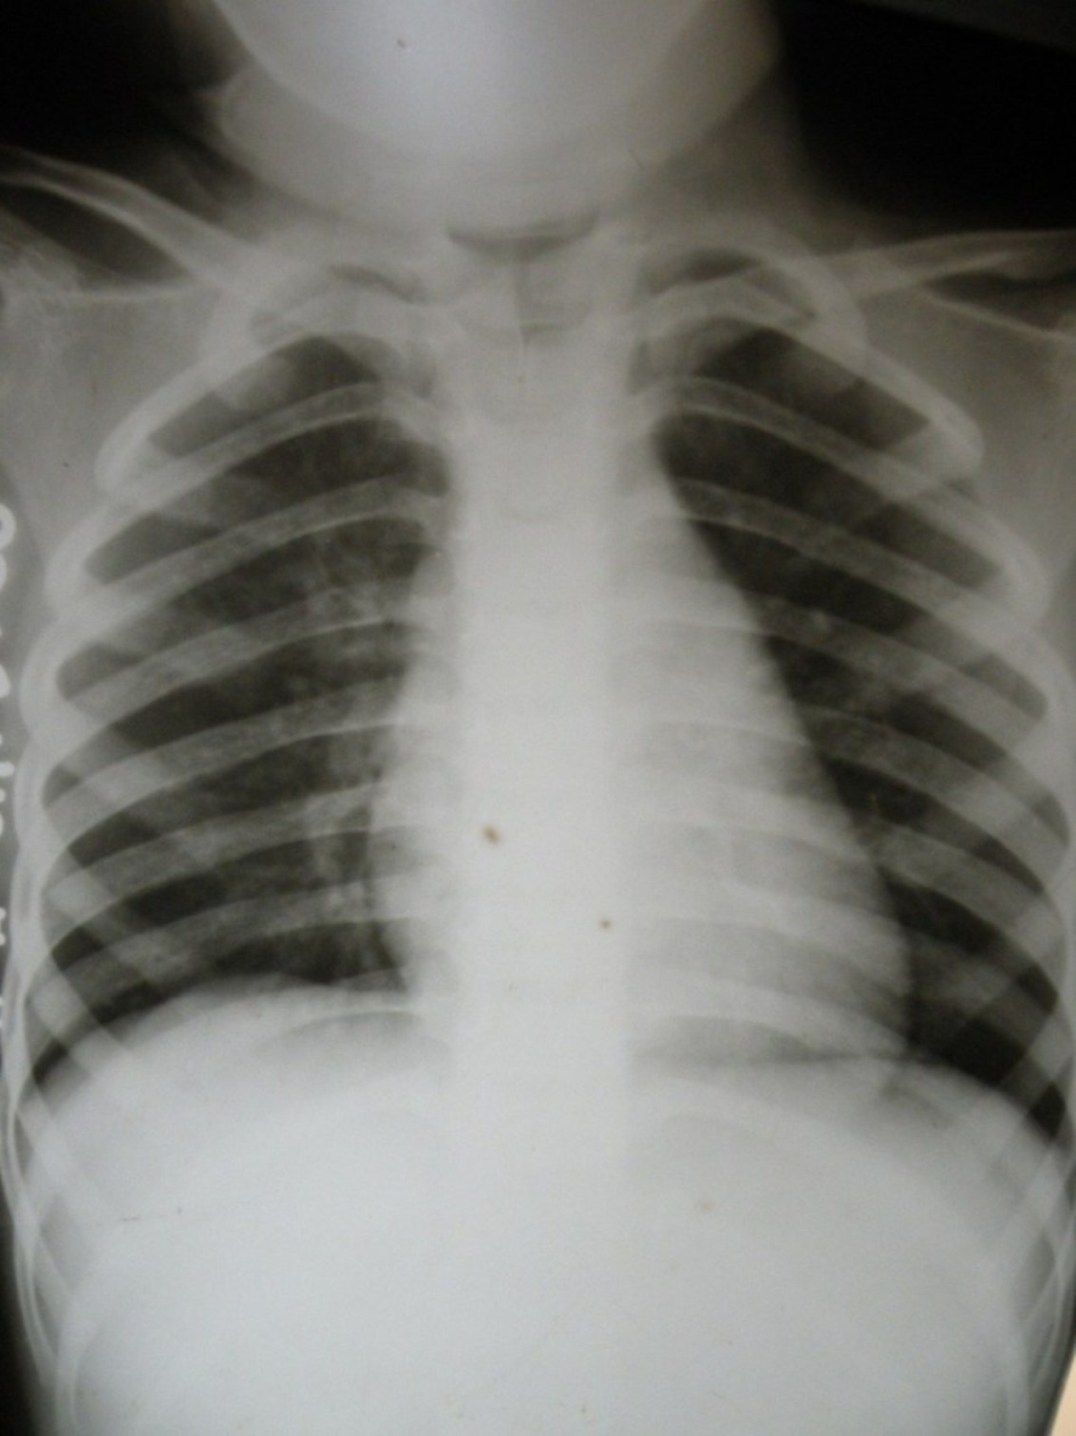

标题: PED1838:男,2岁,咳嗽2月余 [打印本页]

标题: PED1838:男,2岁,咳嗽2月余

请看看t1 t2 后是什么?

脊椎裂?

支持脊椎裂

支持脊椎裂。

首选----声门裂影像     次选---脊椎裂

支持脊柱裂。

首选----声门裂影像     次选---脊椎裂!支持!

先天脊椎隐裂